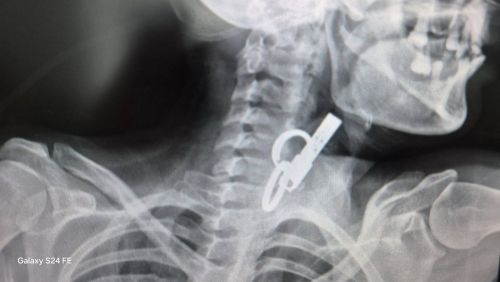

В одній із комунальних лікарень Тернопільської області лікарі врятували життя пацієнта, який проковтнув ключі. Про незвичайний випадок повідомили у Гусятинській комунальній лікарні.

Завдяки наявності сучасного ендоскопічного обладнання та злагодженій роботі команди фахівців у медзакладі успішно провели ендоскопічне видалення великого стороннього тіла зі стравоходу без виконання хірургічного розрізу.